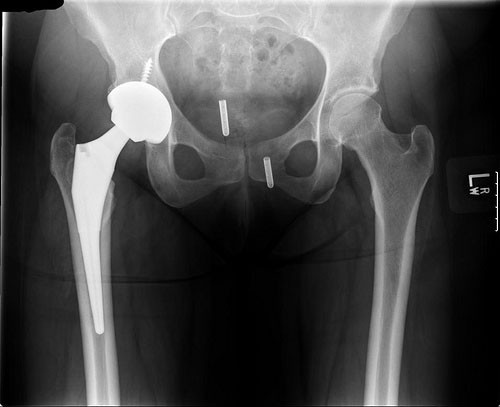

A hip X-ray is a safe and painless test that uses a small amount of radiation to make images of a person's hip joints (where the legs attach to the pelvis). During the examination, an X-ray machine sends a beam of radiation through the pelvic bones and hip joints, and an image is recorded on a computer or special film. This image shows the soft tissues and the bones of the pelvis and hip joints.

The X-ray image is black and white. Dense body parts that block the passage of the X-ray beam through the body, such as bones, appear white on the X-ray image. Softer body tissues, such as the skin and muscles, allow the X-ray beams to pass through them and appear darker. An X-ray technician takes the X-rays.

A hip X-ray can help find the cause of common signs and symptoms such as limping, pain, tenderness, swelling, or deformity in the hip area. It can detect broken bones or a dislocated joint. If hip surgery is required, an X-ray may be taken to plan for the surgery and assess the results of the operation.